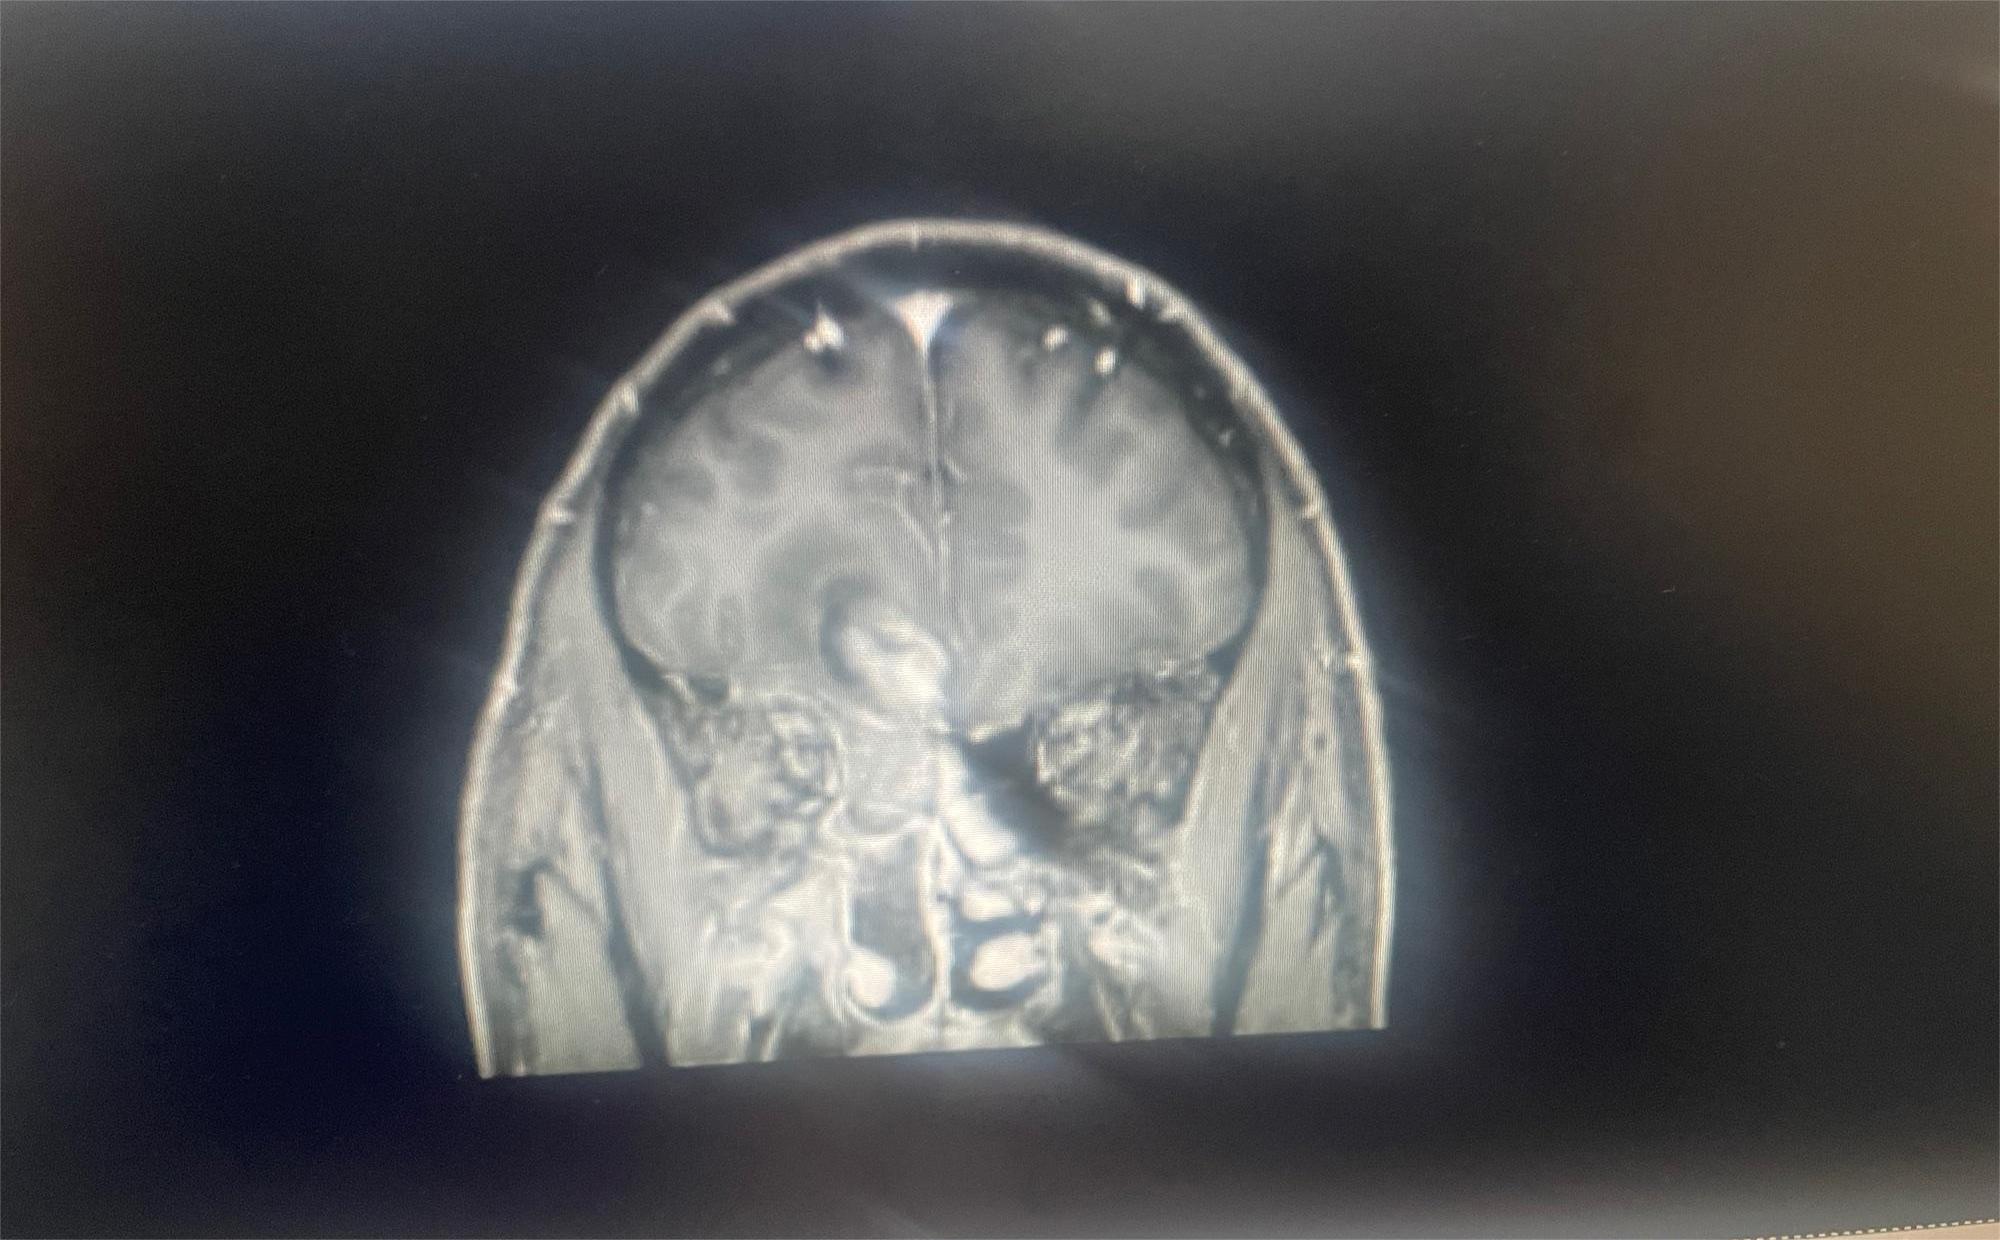

求助有没有比较好医院或者治疗好的方案

共1张

脑部肿瘤求助